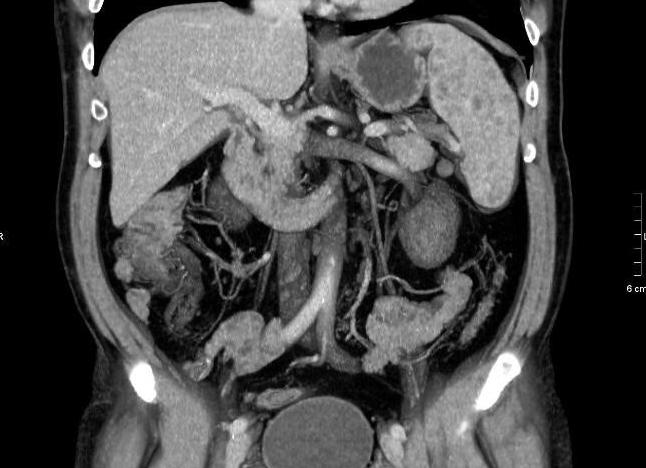

КТ органов грудной клетки называется исследование тканей и внутренних органов человека (в данном случае – области груди) посредством сканирования рентгеновским излучением. Благодаря своей высокой информативности, данный метод является очень востребованным при проведении диагностики болезней, способствуя выявлению с большой точностью аномалий, новообразований, травматических последствий и других нарушений в грудине, легких, пищеводе, дыхательных путях, кровеносных сосудах, плевре, молочных железах, лимфатических узлах, ребрах. Помимо этого, КТ оценивает месторасположение, структуру данных органов, в прямом смысле слова проливая свет на любую патологию тканей и органов, – даже на ранней стадии и протекающую в скрытой форме. Подробнее ...